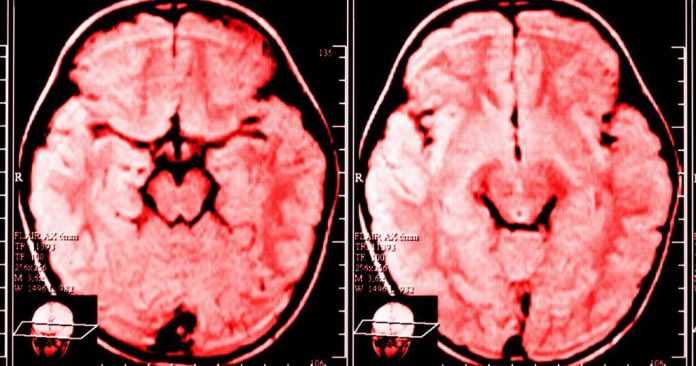

Τα τελευταία 20 χρόνια χάρη στην ταχεία εξέλιξη της απεικόνισης των ημισφαιρίων του εγκεφάλου και της νευροεπιστήμης μπορούμε να πούμε με βεβαιότητα ότι ο εγκέφαλος είναι σε θέση να κάνει ανασχεδιασμό και ότι εμείς είμαστε οι μηχανικοί.

Η νευροπλαστικότητα, δηλαδή ο όρος που χρησιμοποιούμε για να περιγράψουμε την διαρκή αλλαγή στον εγκέφαλο ενός ανθρώπου, είναι εντυπωσιακή και χρήσιμη για πολλούς λόγους: